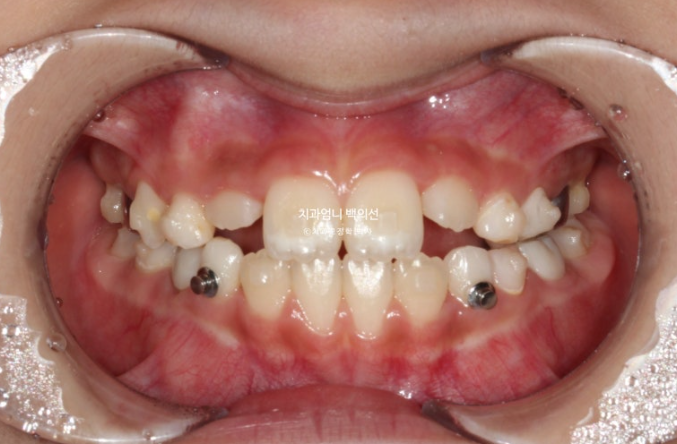

24년 12월부터 25년 6월까지 두번째 세트 19개 장치를 모두 낀 후 모습입니다.

측절치를 포함한 앞니는 잘 배열 되었습니다.

윗니가 아랫니를 잘 덮도록 앞니 교합이 개선되었습니다.

유치송곳니 벌어진 부분은 영구치 송곳니가 나올 때 공간이 부족하지 않도록 의도적으로 형성한 공간입니다.

영구치 맹출 공간은 충분하고 배열과 중심선 교합 모든 게 좋습니다.